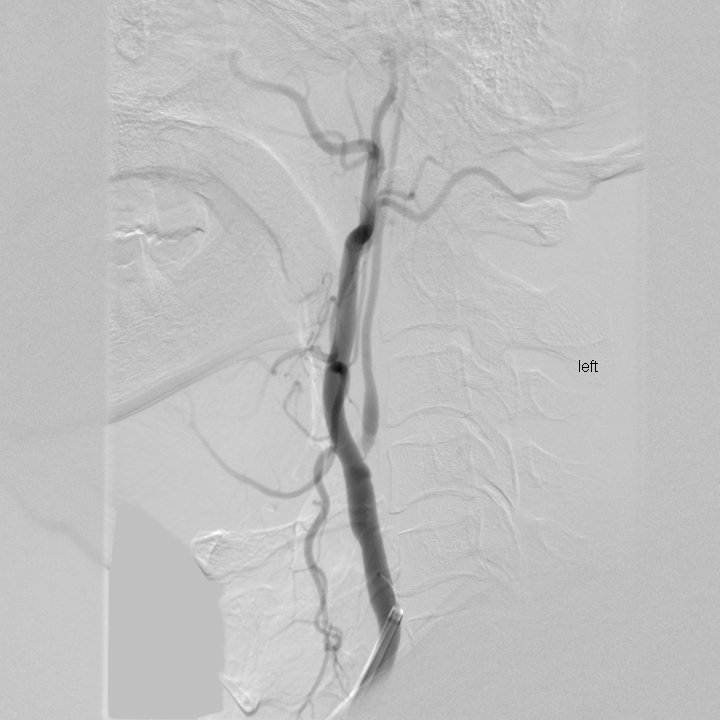

頸動(dòng)脈支架

治療前

治療后